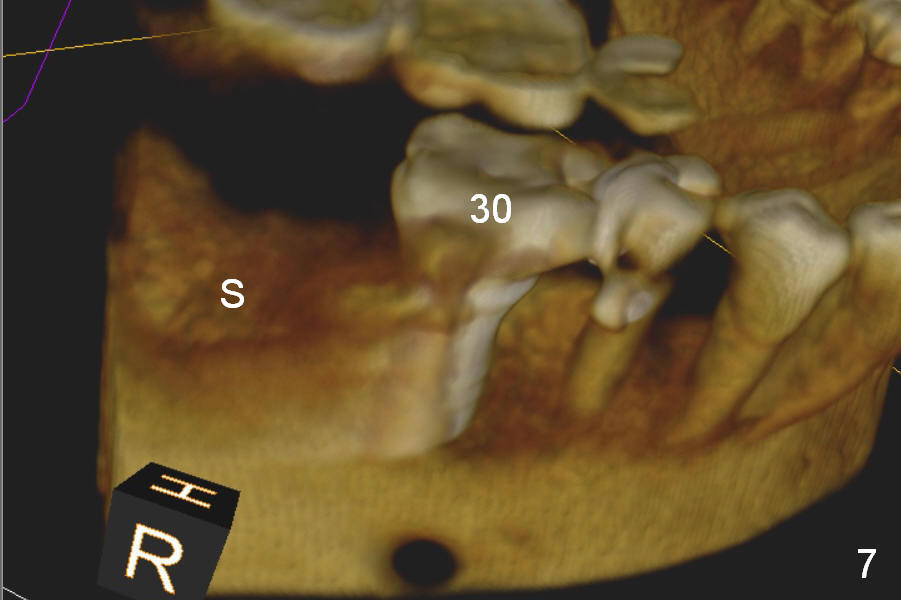

A 75-year-old man has apparent history of bruxism. The distal root of the tooth #31 had vertical fracture after root canal therapy. The tooth was extracted ~ 2 months ago while he returned to home country. It appears that there is buccal plate atrophy (Fig.1 S: socket).

Preop CBCT shows that a 6.4x10 mm implant is appropriate if placed in the middle of the socket (septum), 6 mm from the crown of #30 (Fig.5). Coronal section confirms that because of the lingual slope of the socket, osteotomy should be placed lingually (Fig.6 red line). Three-D image is shown in Fig.7.